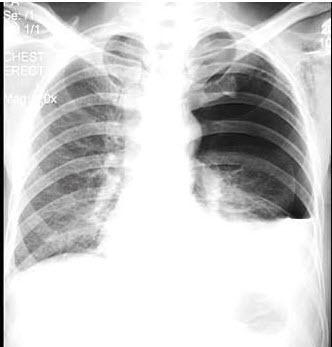

左下肺野可见液-气平面,约与第5前肋相平(蓝色虚线),肺门影不浓.

男,32岁,2天前被人踢伤胸部,感胸闷,呼吸困难,x线检查如图,最可能的